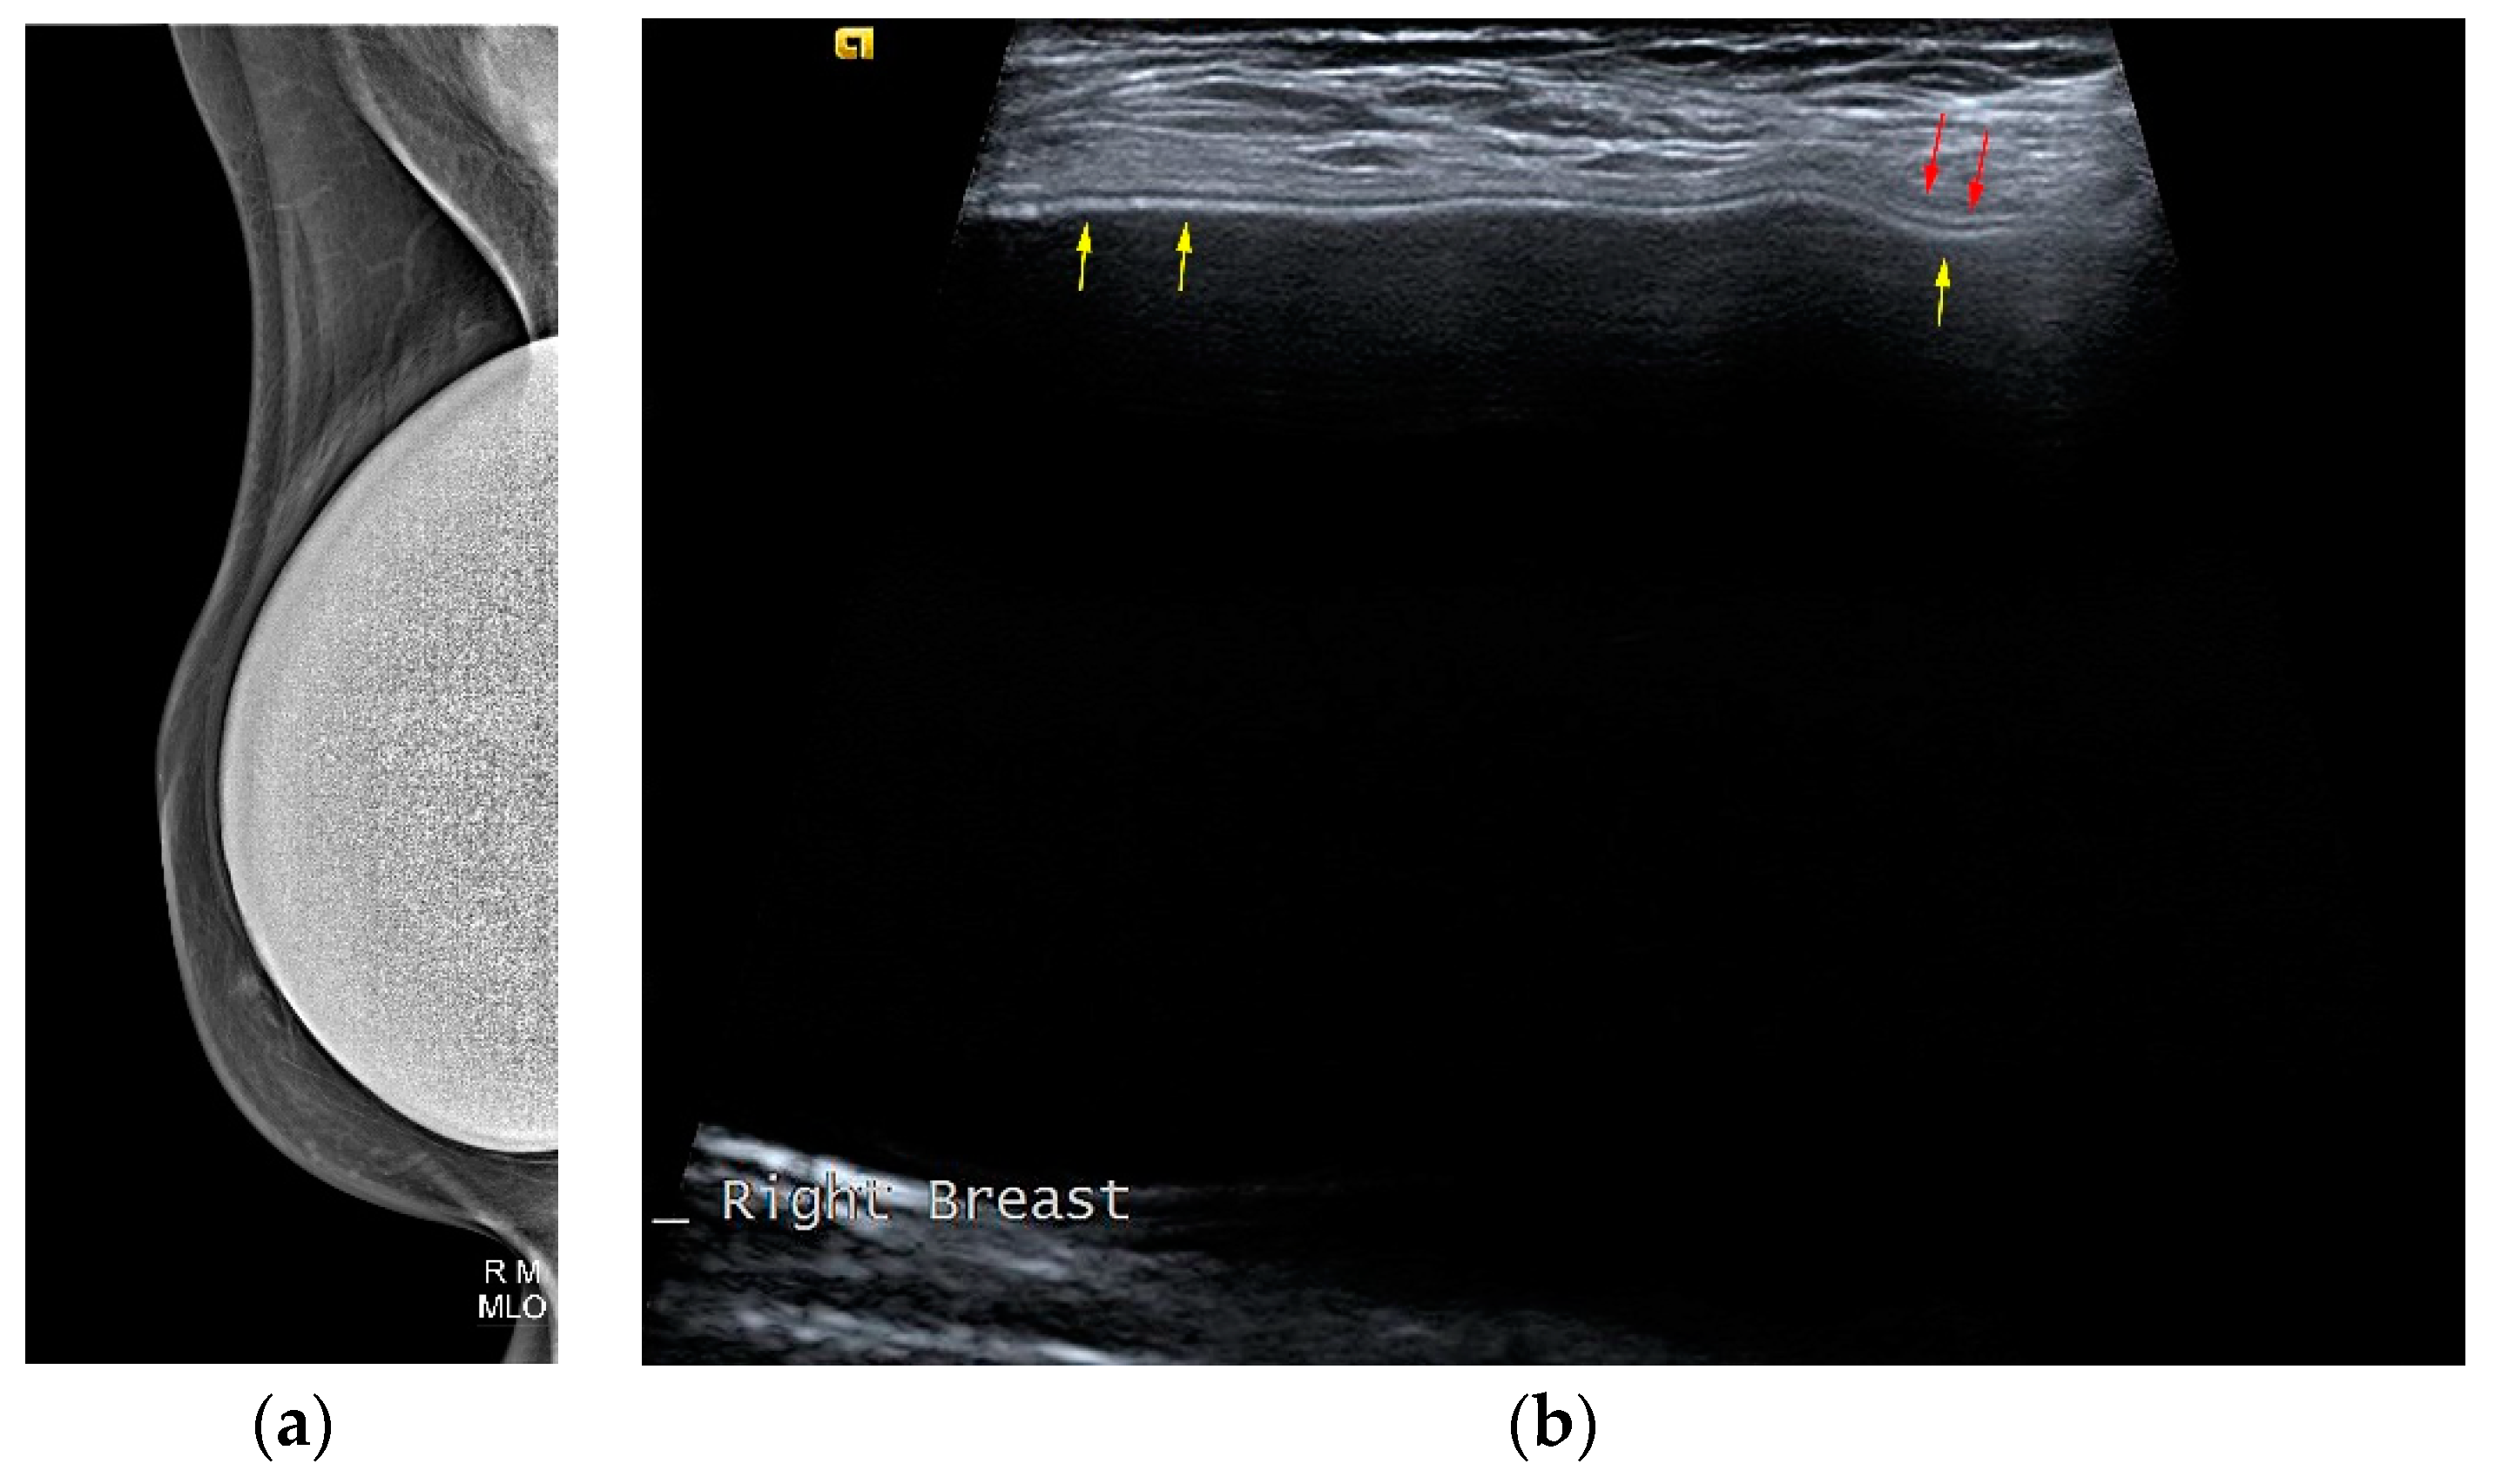

A single lumen implant has an intact shell and is surrounded by a thin fibrous capsule with low signal intensity on all sequences. Saline implants appear with water signal intensity on all sequences, and a valve is recognized within the lumen with low signal intensity, while silicone implants show high signal on T2-weighted and silicone-selective sequences and low signal on T1-weighted sequences (Figure 4). A double lumen implant appears with an inner chamber of silicone with high signal intensity and an outer chamber of saline with water signal intensity (Figure 5) [47,49].